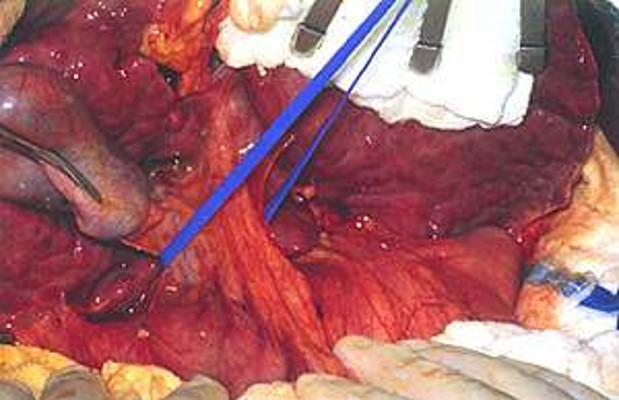

2) The diseased liver is disconnected from blood vessels and ducts, and the vena cava is clamped.

3) The new liver is inserted:

4) Vessels and ducts are attached to the new liver: